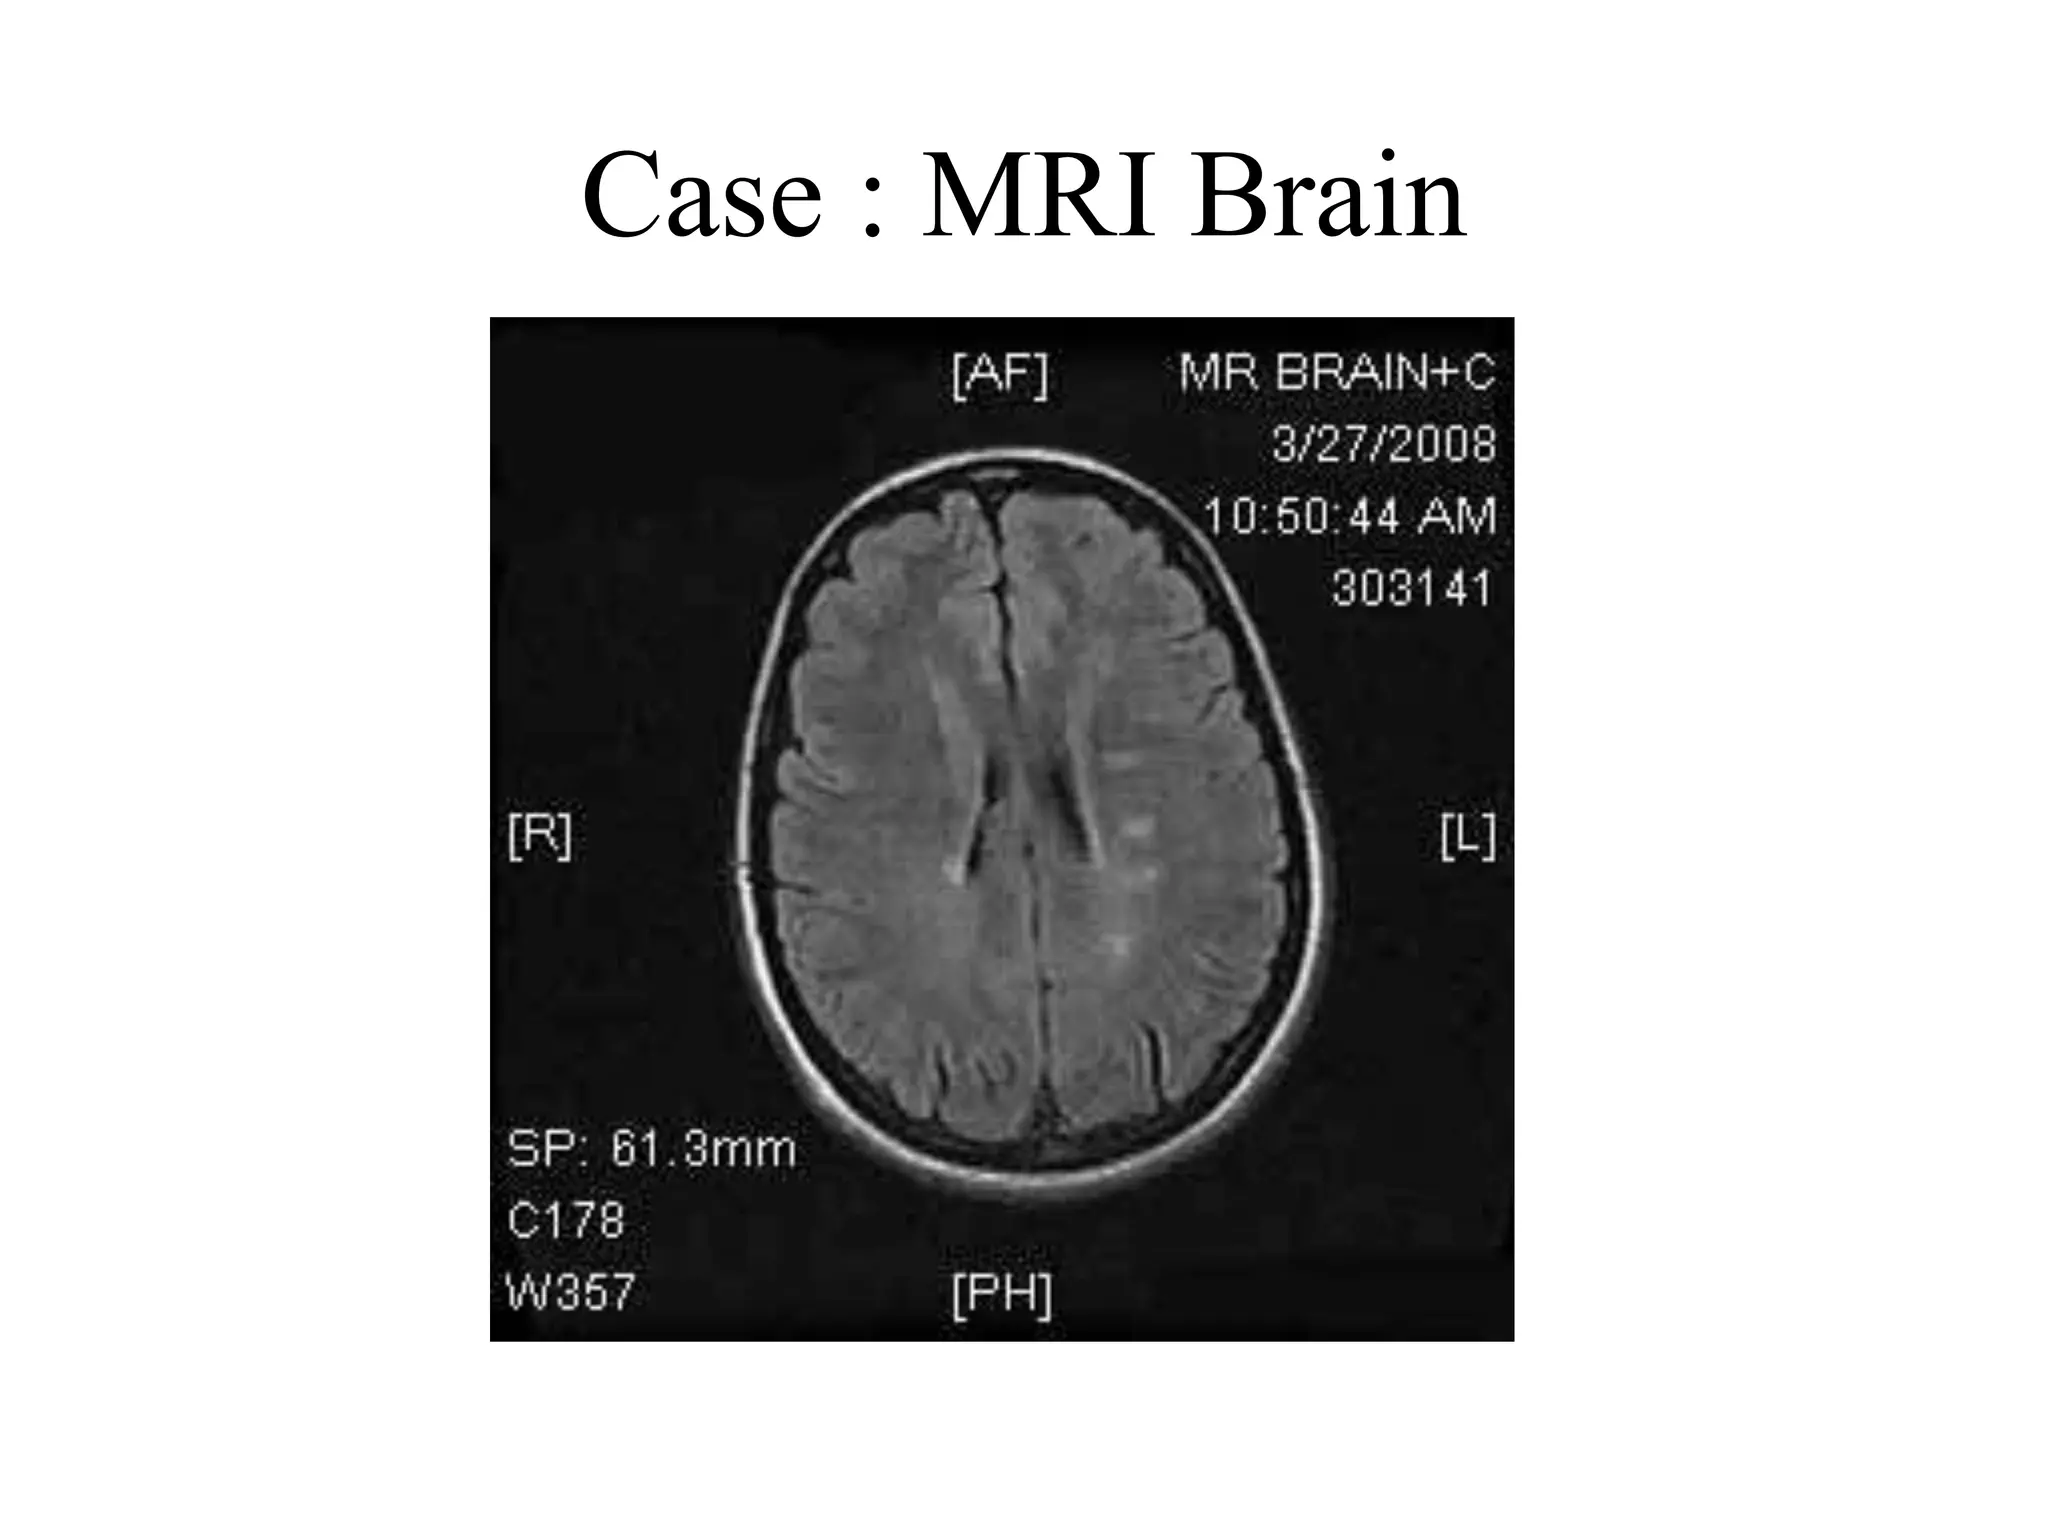

MRI Brain DIS

Case : MRI Brain

CASE • On 18/3/08patient complained of ocular pain on moving the left eye with blurred vision. • 2 days later she developed left frontal headache. • Seen by the ophthalmologist who diagnosed her as optic neuritis and advised to be on neurobion. • She had several attacks of Rt. Upper limb heaviness in the last 2 years, each was lasting for a week. • Her cousin has MS .

CASE : Examination •Her vision was 20/200 in the left eye and 20/40 in the right eye. There was a central scotoma, and red and blue colors were less intense in the left eye. • RAPD on the left • Left fundus: disc is congested and swollen. • Central Scotoma • Treated with pulse IV methylprednisolone for 3 days and improved followed by short prednisolone taper